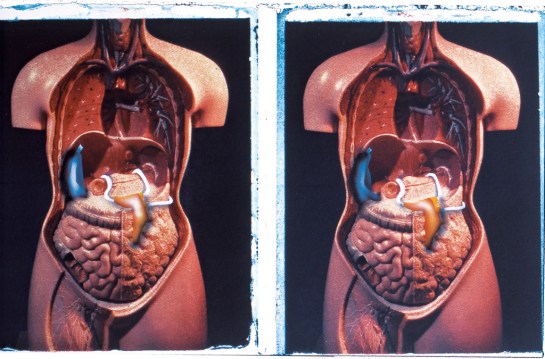

The stereoscopic anatomical drawings describe the apparatus to make an internal architecture. THis sequence of paired drawings discusses the revelation of the architecture in both a practical way but also by implication a sense of the larger spatial consequence of the project. Each pair of drawings has an X-ray and a photographic illustration of the position the body has to hold to take that X-ray. The base images (except for the final X-ray) are taken from Positioning in Radiography by K.C. Clark (1949 edition). Francis Bacon worked from images in the 1939 edition of the same book.

Each X-Ray shows parts of the new body apparatus but they are available to this sort of inspection selectively, so not everything is visible. The positioning photographs display a formal transparency of the apparatus, again selectively as only those parts that press against the skin are visible.

In the positioning picture (2B) you can see a filter under her skin just above her forearm and the top of the breathing/cooling components just below her collar bone, the piece that is visible in the X-ray.

X-Ray 3A is not from Positioning in Radiography, but 3B is, the positioning to take the image in 3A. The X-Ray shows the selective revelation of the intestines through the agency of a barium meal – tissue that would otherwise be transparent to X-Ray shows up due to the meal. The image is unlikely, as the synthetic organs of the new apparatus should divert toxins through the synthetic system (and therefore reveal them more fully) so we have to assume that the apparatus has been turned off to check the natural organs. In the positioning photograph you can again see discrete bumps around her waist and abdomen where the apparatus pushes into the skin.